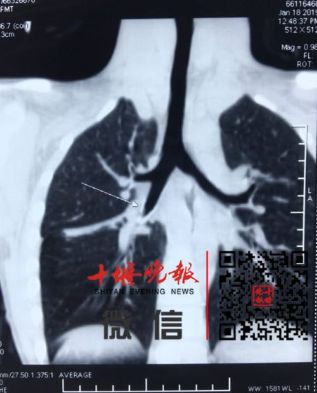

今年1月,郧西8岁女童反复咳嗽,太和医院专家检查时,发现其肺部有像吹哨子一样的声音。原来一支笔头卡在了女童的支气管中,且已引起反复炎症。最终医生在女童胸壁开了3个孔才将异物取出。

片子中可以看到女童支气管被笔帽卡住